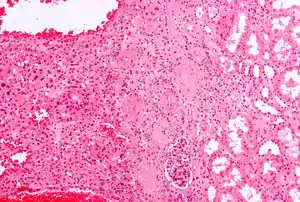

Micrograph of a renal oncocytoma. H&E stain.

Micrograph of a renal oncocytoma. H&E stain. Gross appearance of the cut surface of a nephrectomy specimen containing a renal oncocytoma. Note the rounded contour, the mahogany colour and the central scar.